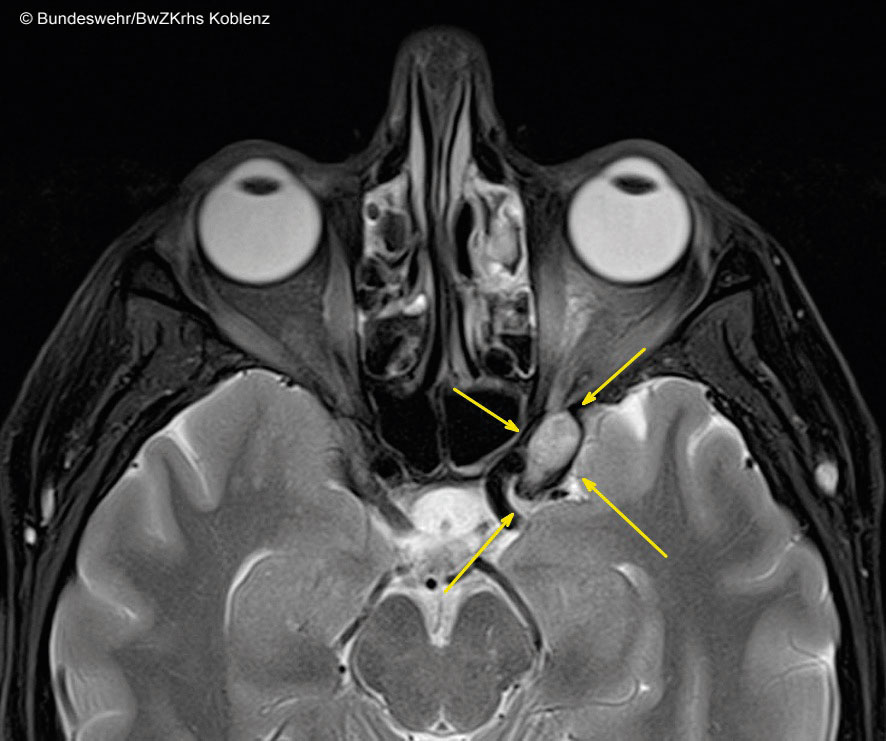

Eine 50-jährige Frau musste wegen einer akuten Neuropathia vestibularis in den MRT. Als Zufallsbefund entdeckten die Radiologen eine glatt begrenzte, ca. 17 x 10 mm große Formation unterhalb des linken Keilbeines, die an die Fissura orbitalis superior und den Sinus cavernosus grenzte (s. Abb. 2). Morphologisch sah es nach einem kavernösen Hämangiom mit Ursprung im Sinus cavernosus aus. Man entschied sich konservativ vorzugehen und die asymptomatische Patientin regelmäßig klinisch und radiologisch zu kontrollieren. Bisher blieb der Befund konstant. Eine OP ist erst bei einer deutlichen Progredienz vorgesehen.